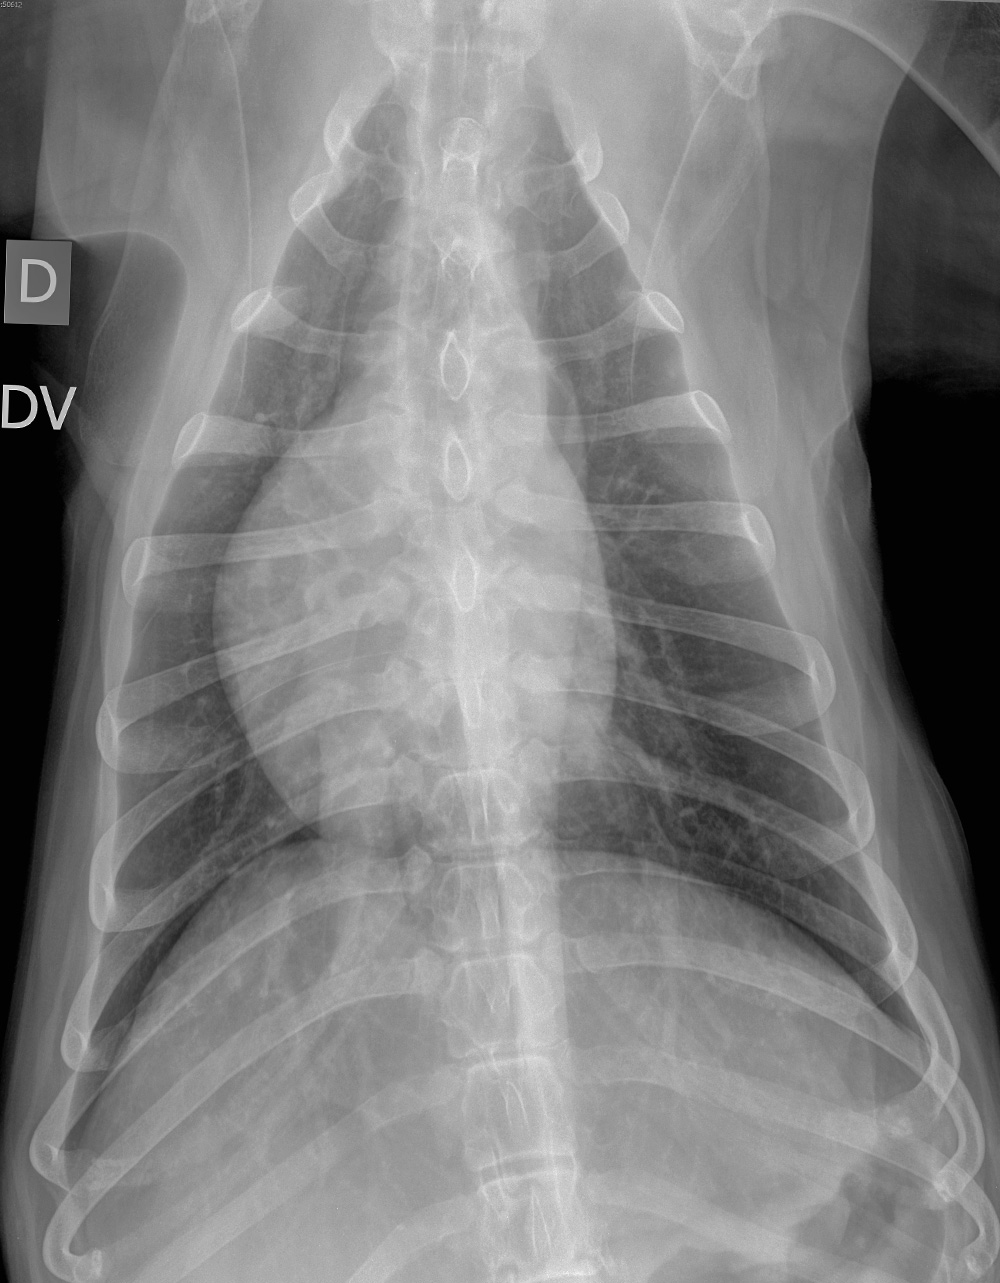

DV

Oui, costales sur les deux premières paires ? J y vois une ostelyse avec perte de continuité et une image de déformation de la côté à sa base avec une corticale déformée et amincie voire absente. Et quid de la lésion entre les deux dernières sternebres? Elle semble moins agressive car à cheval sur les deux sternebres. Osteo prolifération bénigne?

D ailleurs ne s agirait il pas de réglages radiographiques pour de l exploration osseuse… Merci!

Salut Marie Hélène ! Bienvenu sur Animages ! Je ne vois pas d’ostéolyse costale, mais peut-être pourrais-tu m’envoyer une image avec des flèches (via une capture d’écran) ciblant la région qui te chatouille ? Sinon, la réaction intersternébrale est de nature dégénérative et sans conséquence clinique. Les structures osseuses apparaissent assez évidentes en raison des filtres employés avec ce système de haute définition.